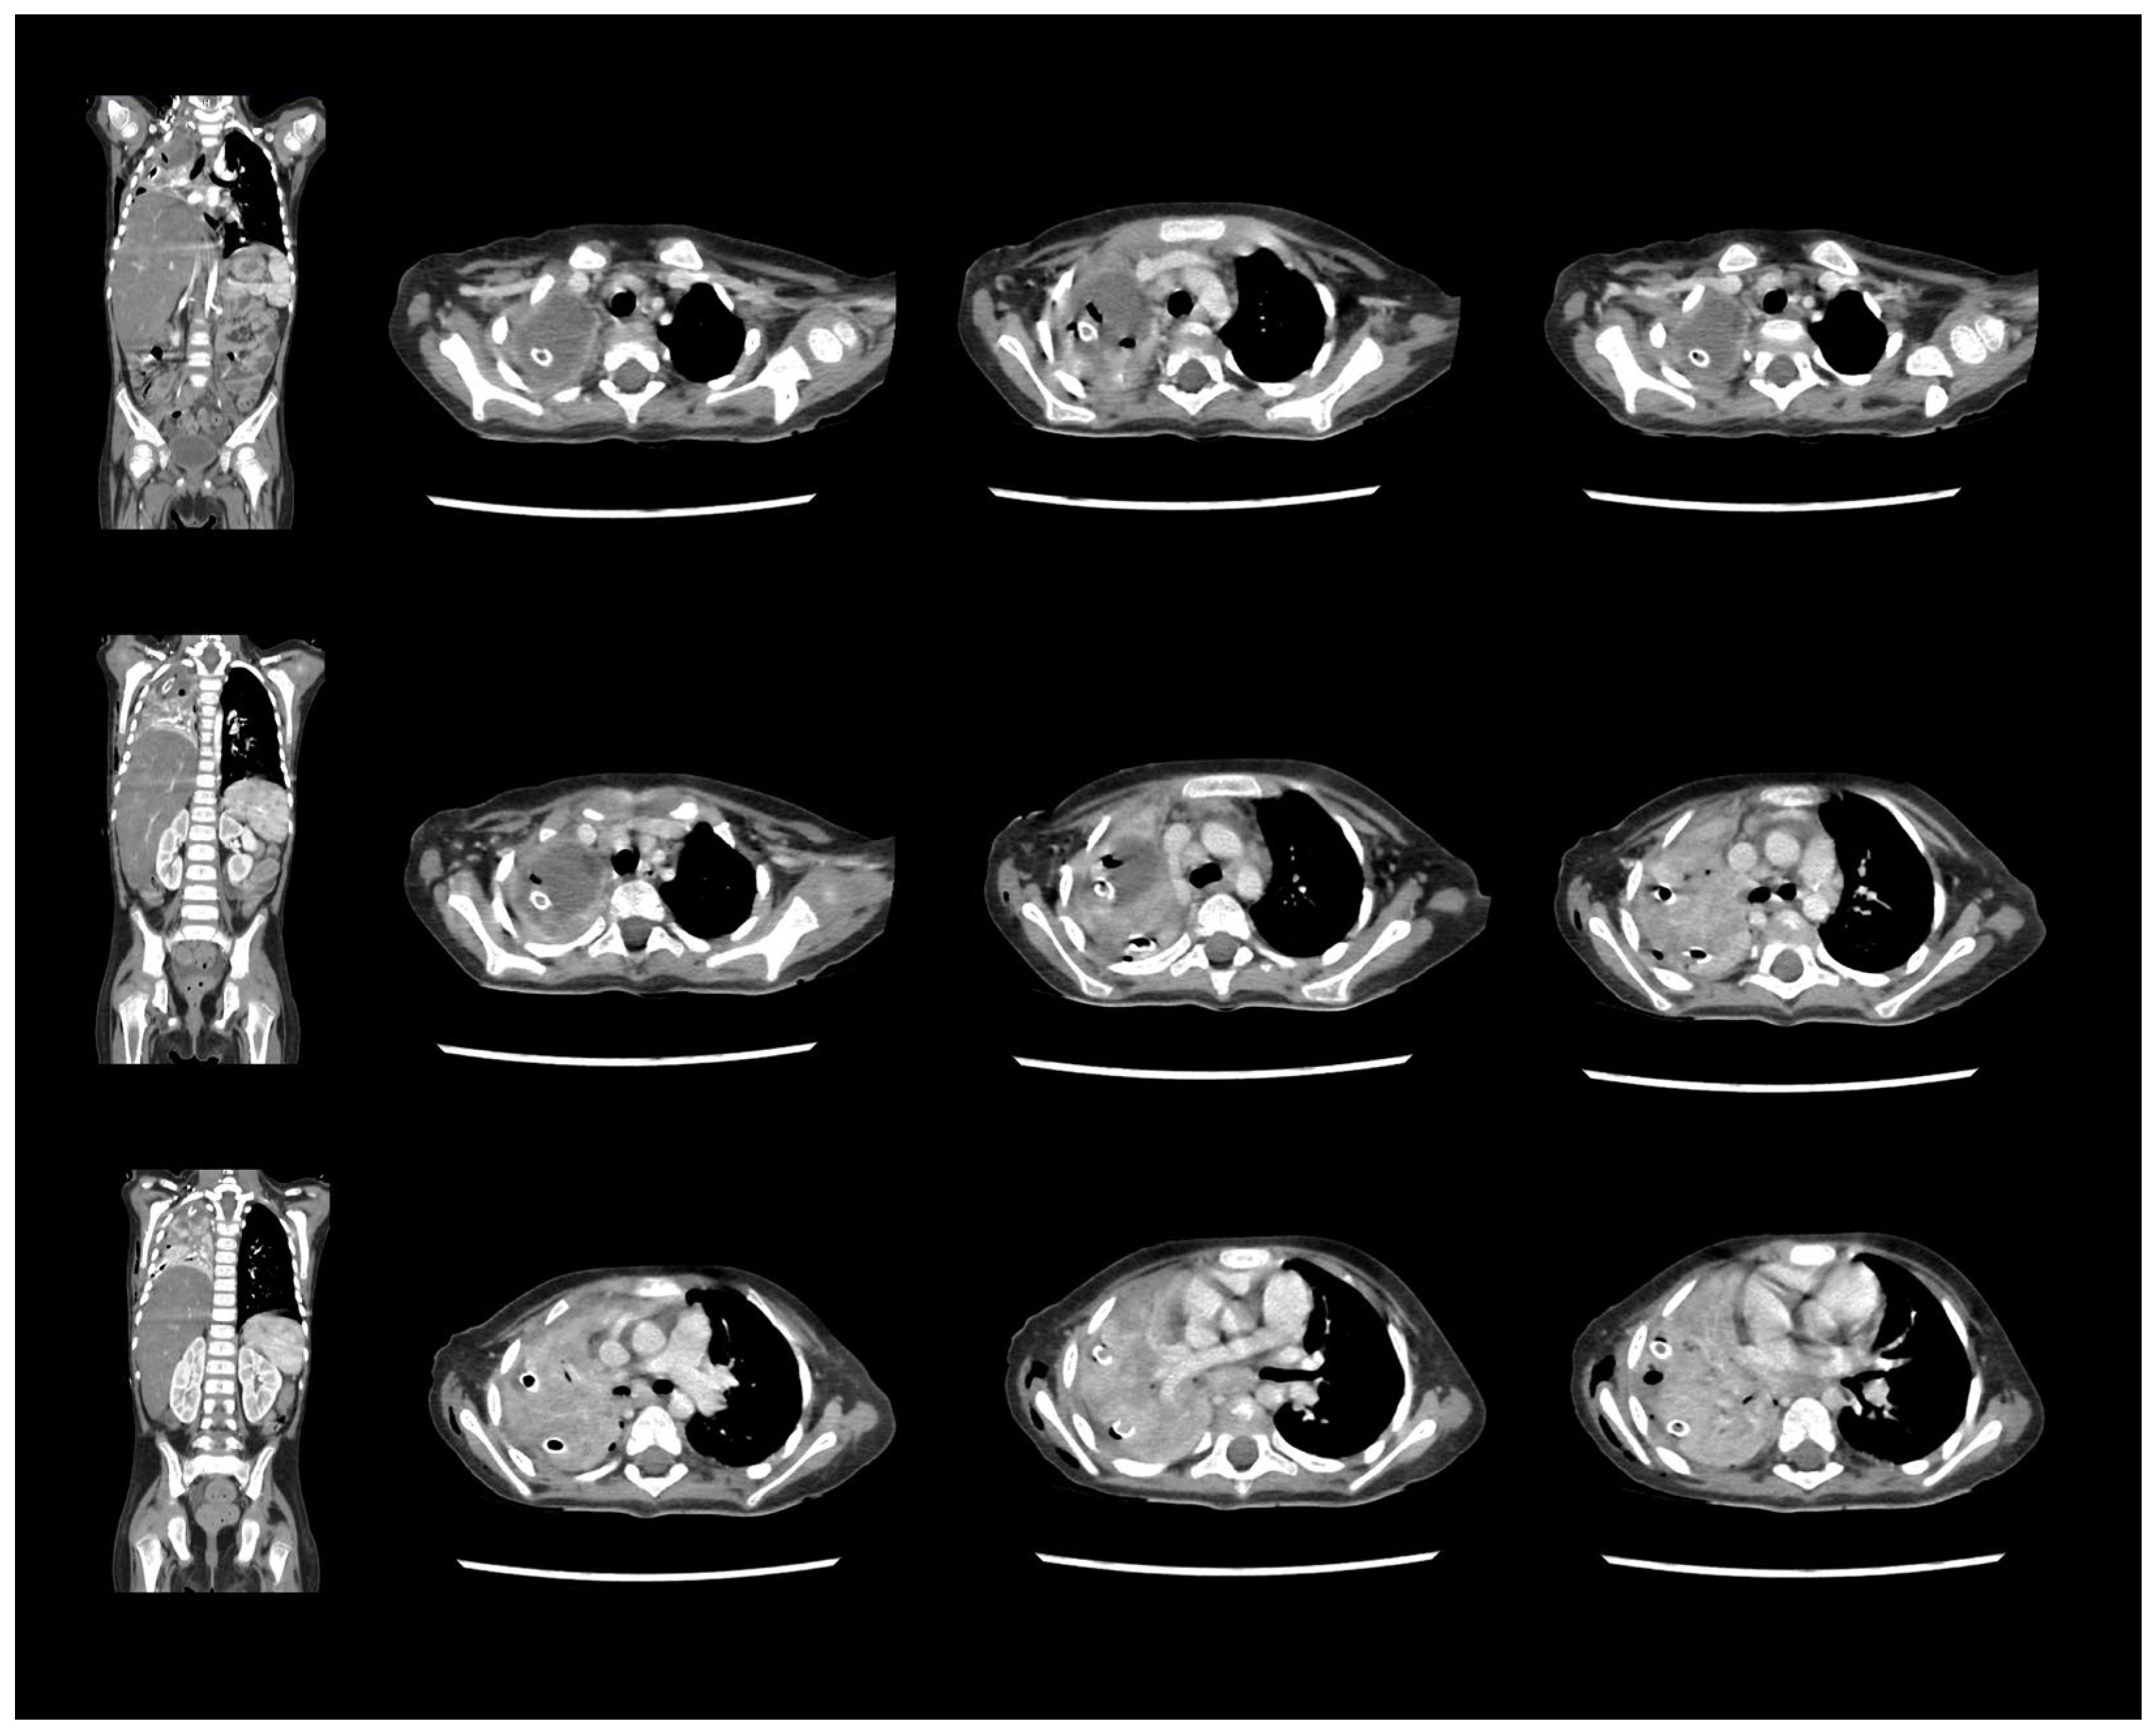

A Rare Case of Rhizomucor pusillus Infection in a 3-Year-Old Child with Acute Lymphoblastic Leukemia, Presenting with Lung and Brain Abscesses—Case Report

Pahnev, Y.; Avramova, B.; Gabrovska, N.; Dontcheva, Y.; Tacheva, G.; Minkin, K.; Kreipe, H.; Yurukova, N.; Penkov, M.; Kartulev, N.; et al. A Rare Case of Rhizomucor pusillus Infection in a 3-Year-Old Child with Acute Lymphoblastic Leukemia, Presenting with Lung and Brain Abscesses—Case Report. Infect. Dis. Rep. 2026, 18, 2. https://doi.org/10.3390/idr18010002